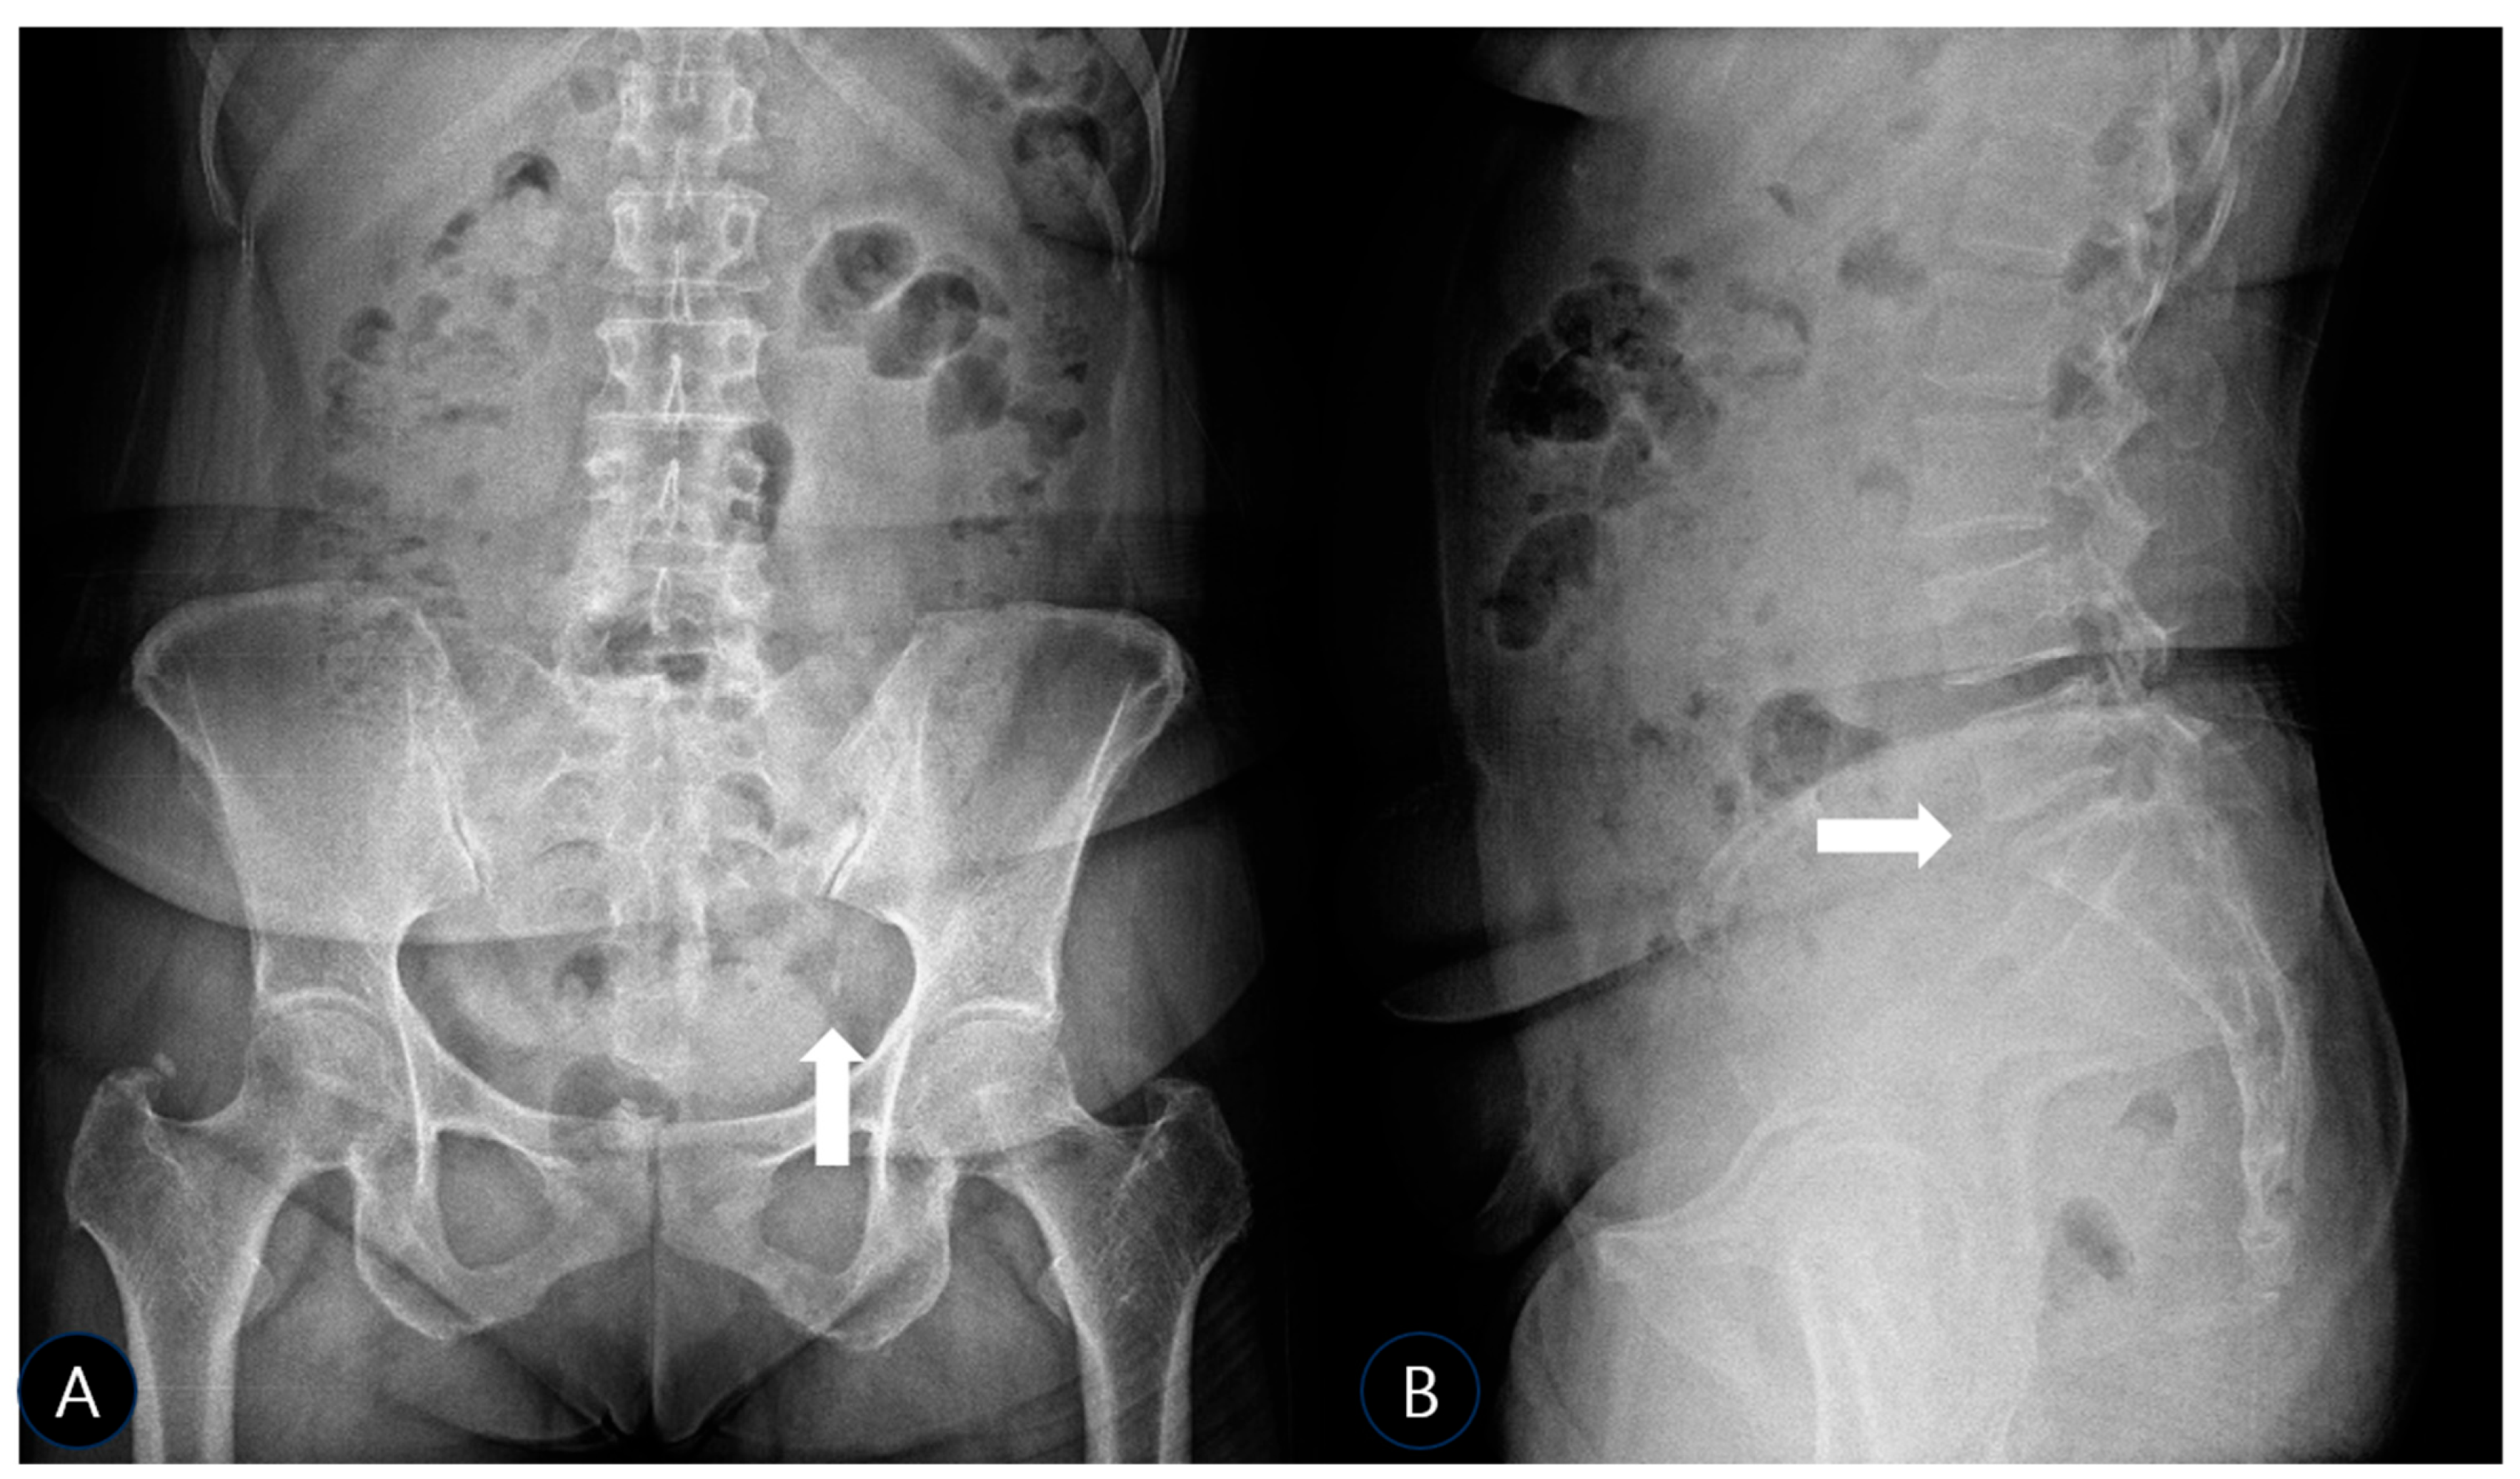

To precisely characterize this calcification and its relationship to the sciatic nerve, a comprehensive Musculoskeletal Ultrasound (MSK-US) examination was performed utilizing a curvilinear probe (C3–5). The sciatic nerve was systematically traced in short-axis from the infrapiriformis space distally towards the subgluteal fold. At the level of the ischial spine, a conspicuous, hyperechoic focus with dense posterior acoustic shadowing was identified embedded within the fibers of the SSL. This focus measured approximately 10 mm in its long axis and 3 mm in the anterior–posterior dimension and was consistent with a macroscopic calcific deposit within the ligament substance. The sciatic nerve was observed as a hyperechoic structure and showed prominent morphologic alteration compared to the healthy side (Figure 2A). In transverse view, it appeared markedly swollen, with an increased anteroposterior diameter of approximately 12 mm (compared to 8 mm on the asymptomatic contralateral side). There was a pronounced loss of the normal heterogeneous fascicular echotexture, sonographic findings highly consistent with reactive neuritis, edema, and possible fibrosis secondary to chronic adjacent mechanical irritation (Figure 2A). Dynamic assessment during passive internal rotation and adduction of the hip (simulating the FAIR position) showed a clear reduction in the normal gliding motion of the sciatic nerve against the rigid, unyielding calcified ligament, providing a dynamic correlate to the entrapment.

Figure 2. (A) Musculoskeletal ultrasound (MSK-US) image of the left sacrospinous ligament in long-axis view, demonstrating a hyperechoic calcific deposit (arrow) with dense posterior acoustic shadowing. The adjacent sciatic nerve appears swollen and hypoechoic compared to the contralateral side. (B) Schematic illustration of the anatomical relationship between the calcified ligament and the sciatic nerve for better localization. (The probe position is indicated in a schematic drawing on the ultrasound image).